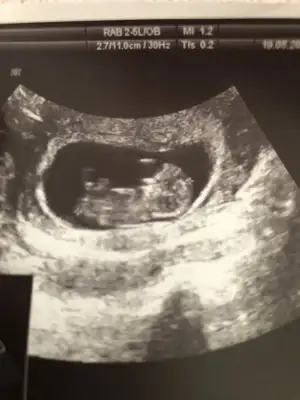

Arkadaşlar 11 hafta 3 günlük hamileyim rica etsem cinsiyet tahmini yapabilir misiniz? Resim ekleyememişim şimdi ekledim şimdiden teşekkürler![]()

P pembemum Konu sahibine yazdım benŞimdilik kız gibi sanki 12-13 haftasınıda paylaşın

kıza benziyor.Arkadaşlar 11 hafta 3 günlük hamileyim rica etsem cinsiyet tahmini yapabilir misiniz? Resim ekleyememişim şimdi ekledim şimdiden teşekkürler![]()